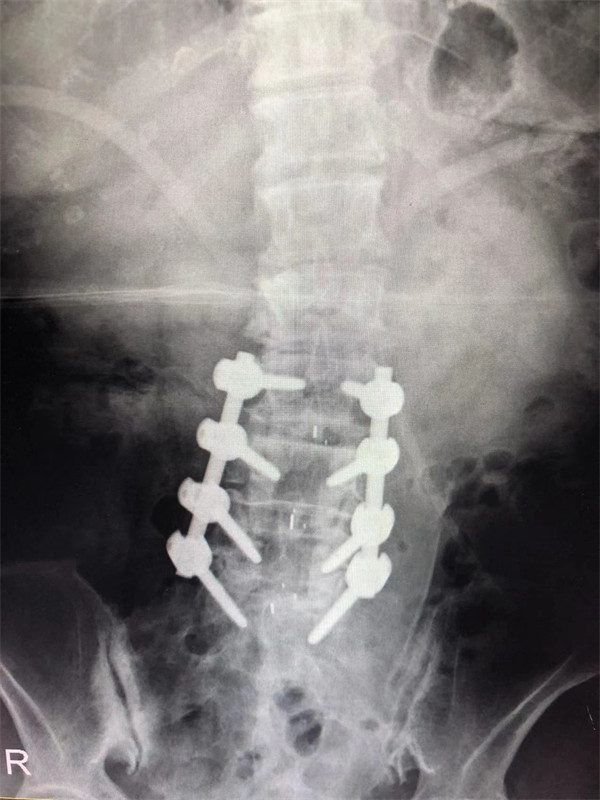

戈才華主任團隊討論病情及手術風險,并與麻醉科醫(yī)生多次討論術中麻醉風險,經過詳盡周密的布置之后,最終給阿婆在全麻下進行腰3/4,4/5,腰5/骶1腰椎椎體間融合術。

手術后↓